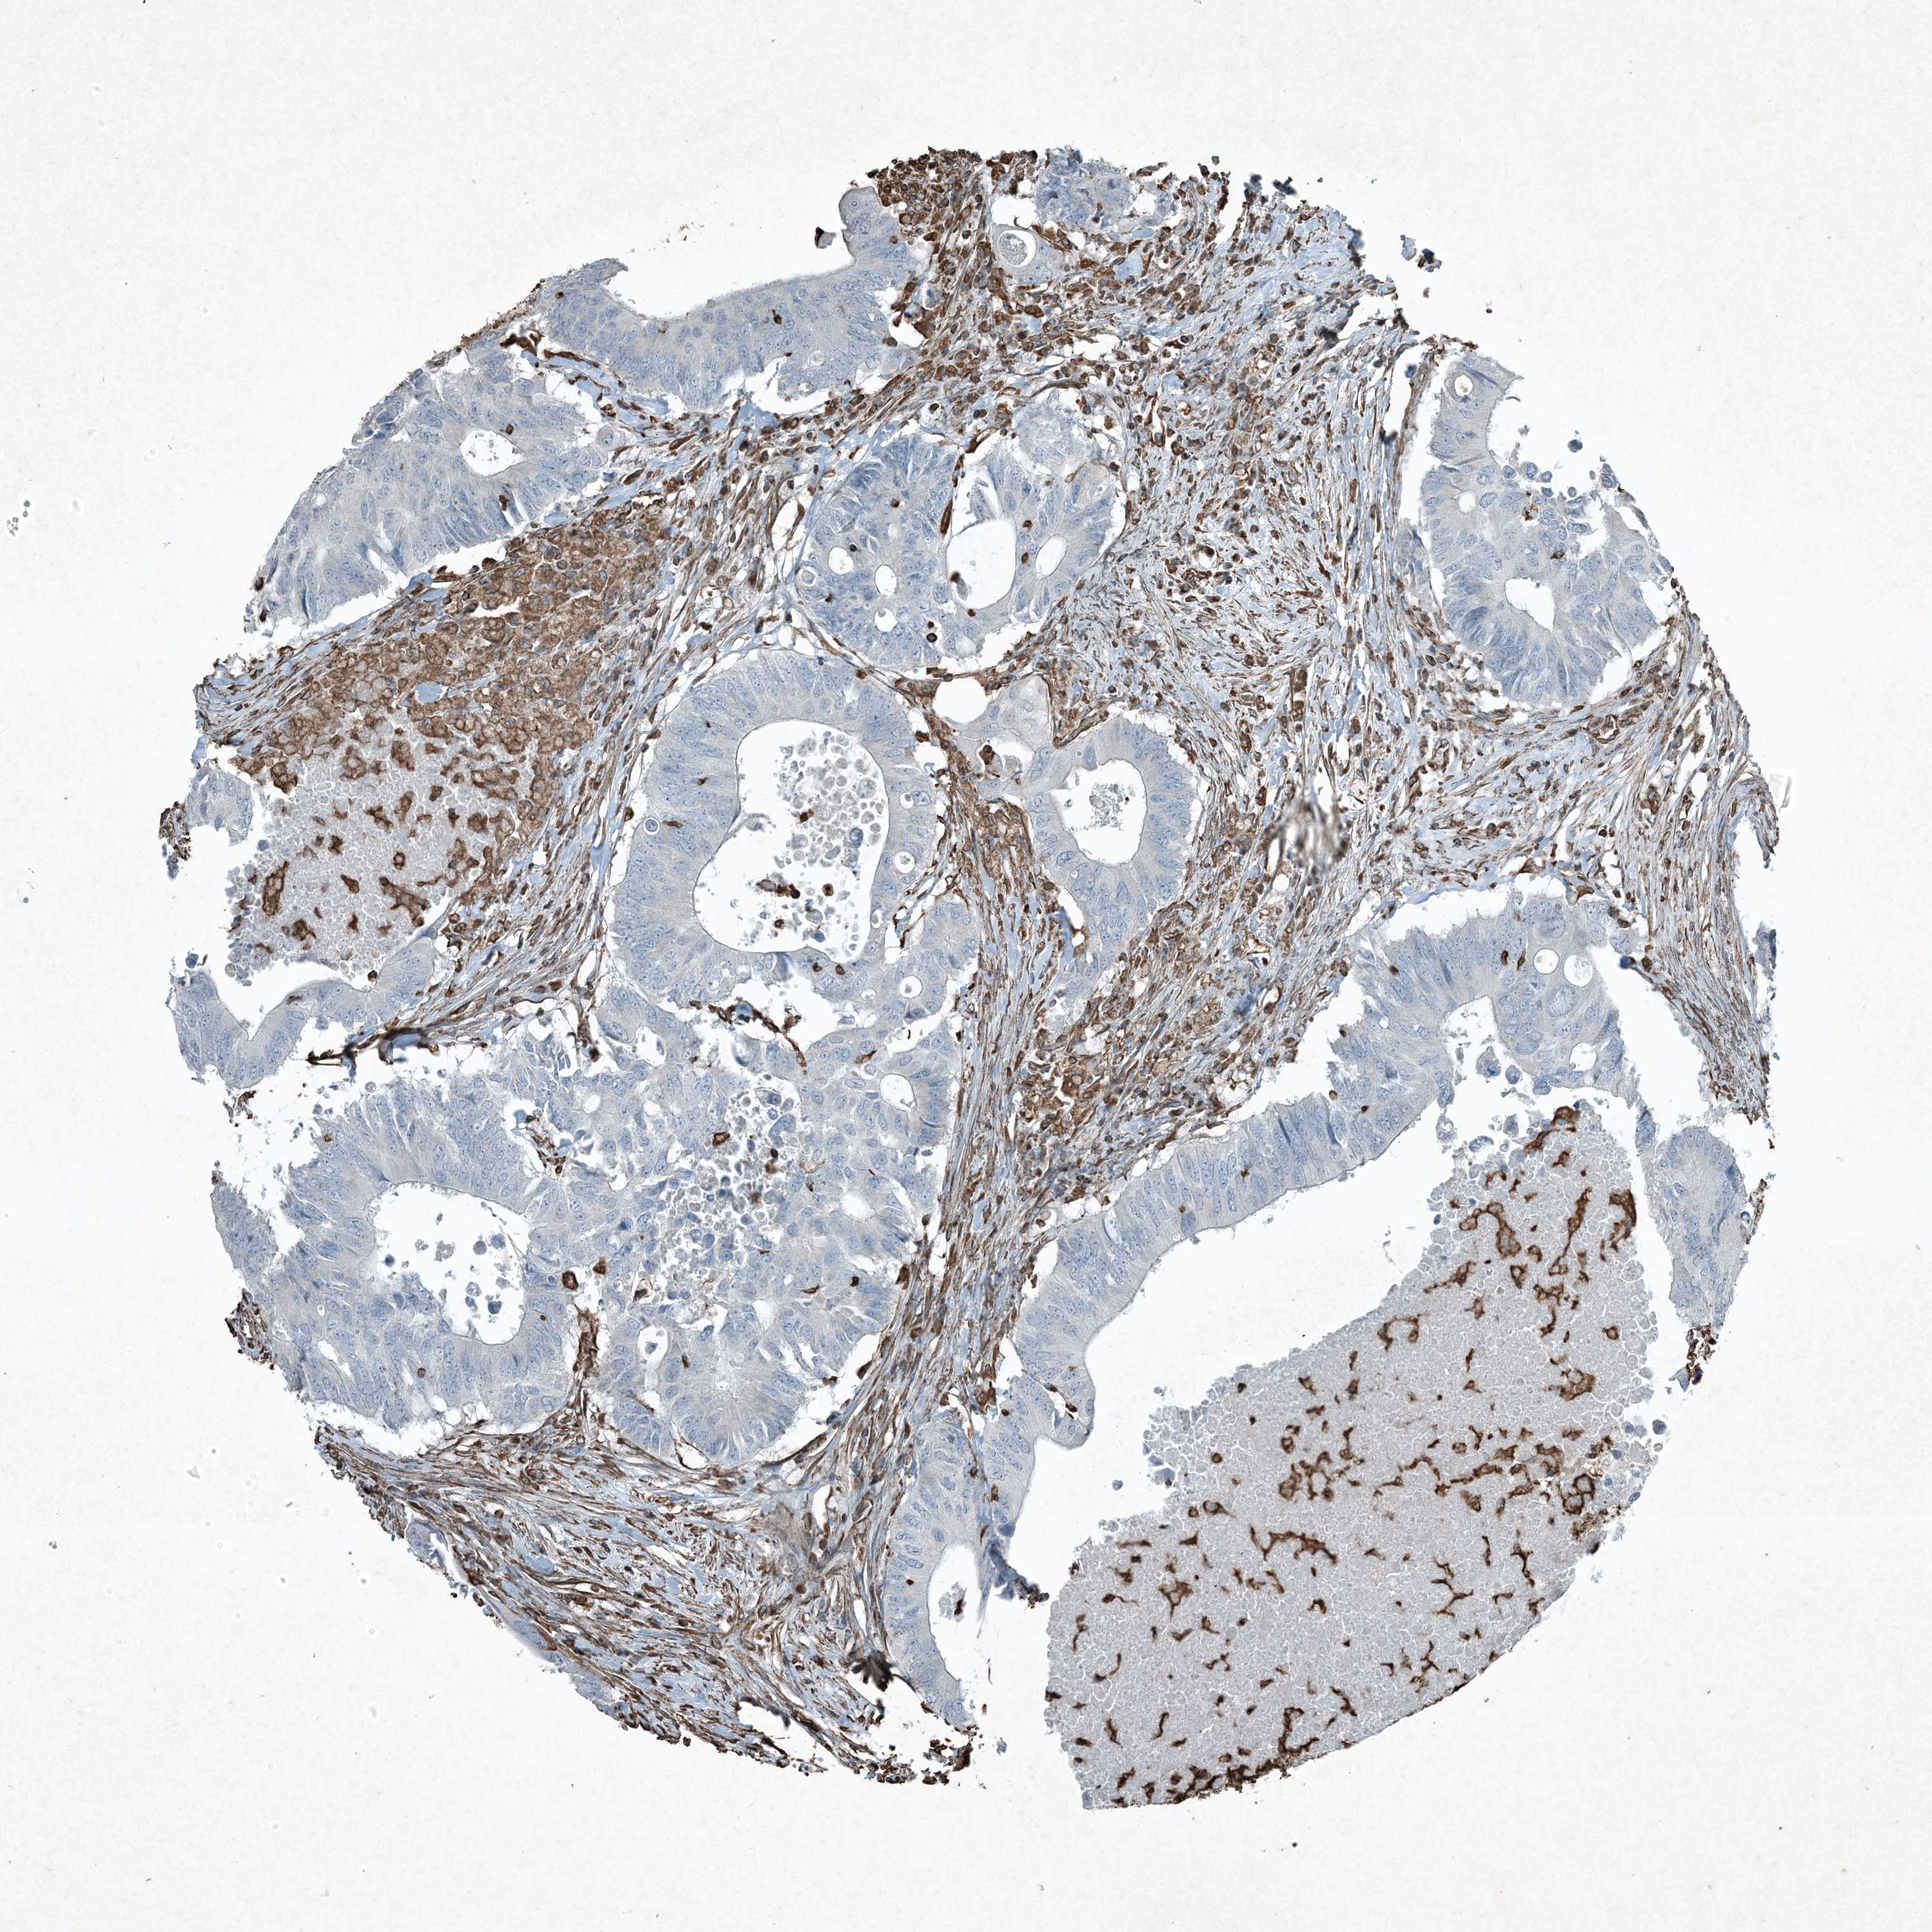

CANCER COLORECTAL CANCER Show tissue menu

Colorectal cancer

Human cancer

Colon adenocarcinoma